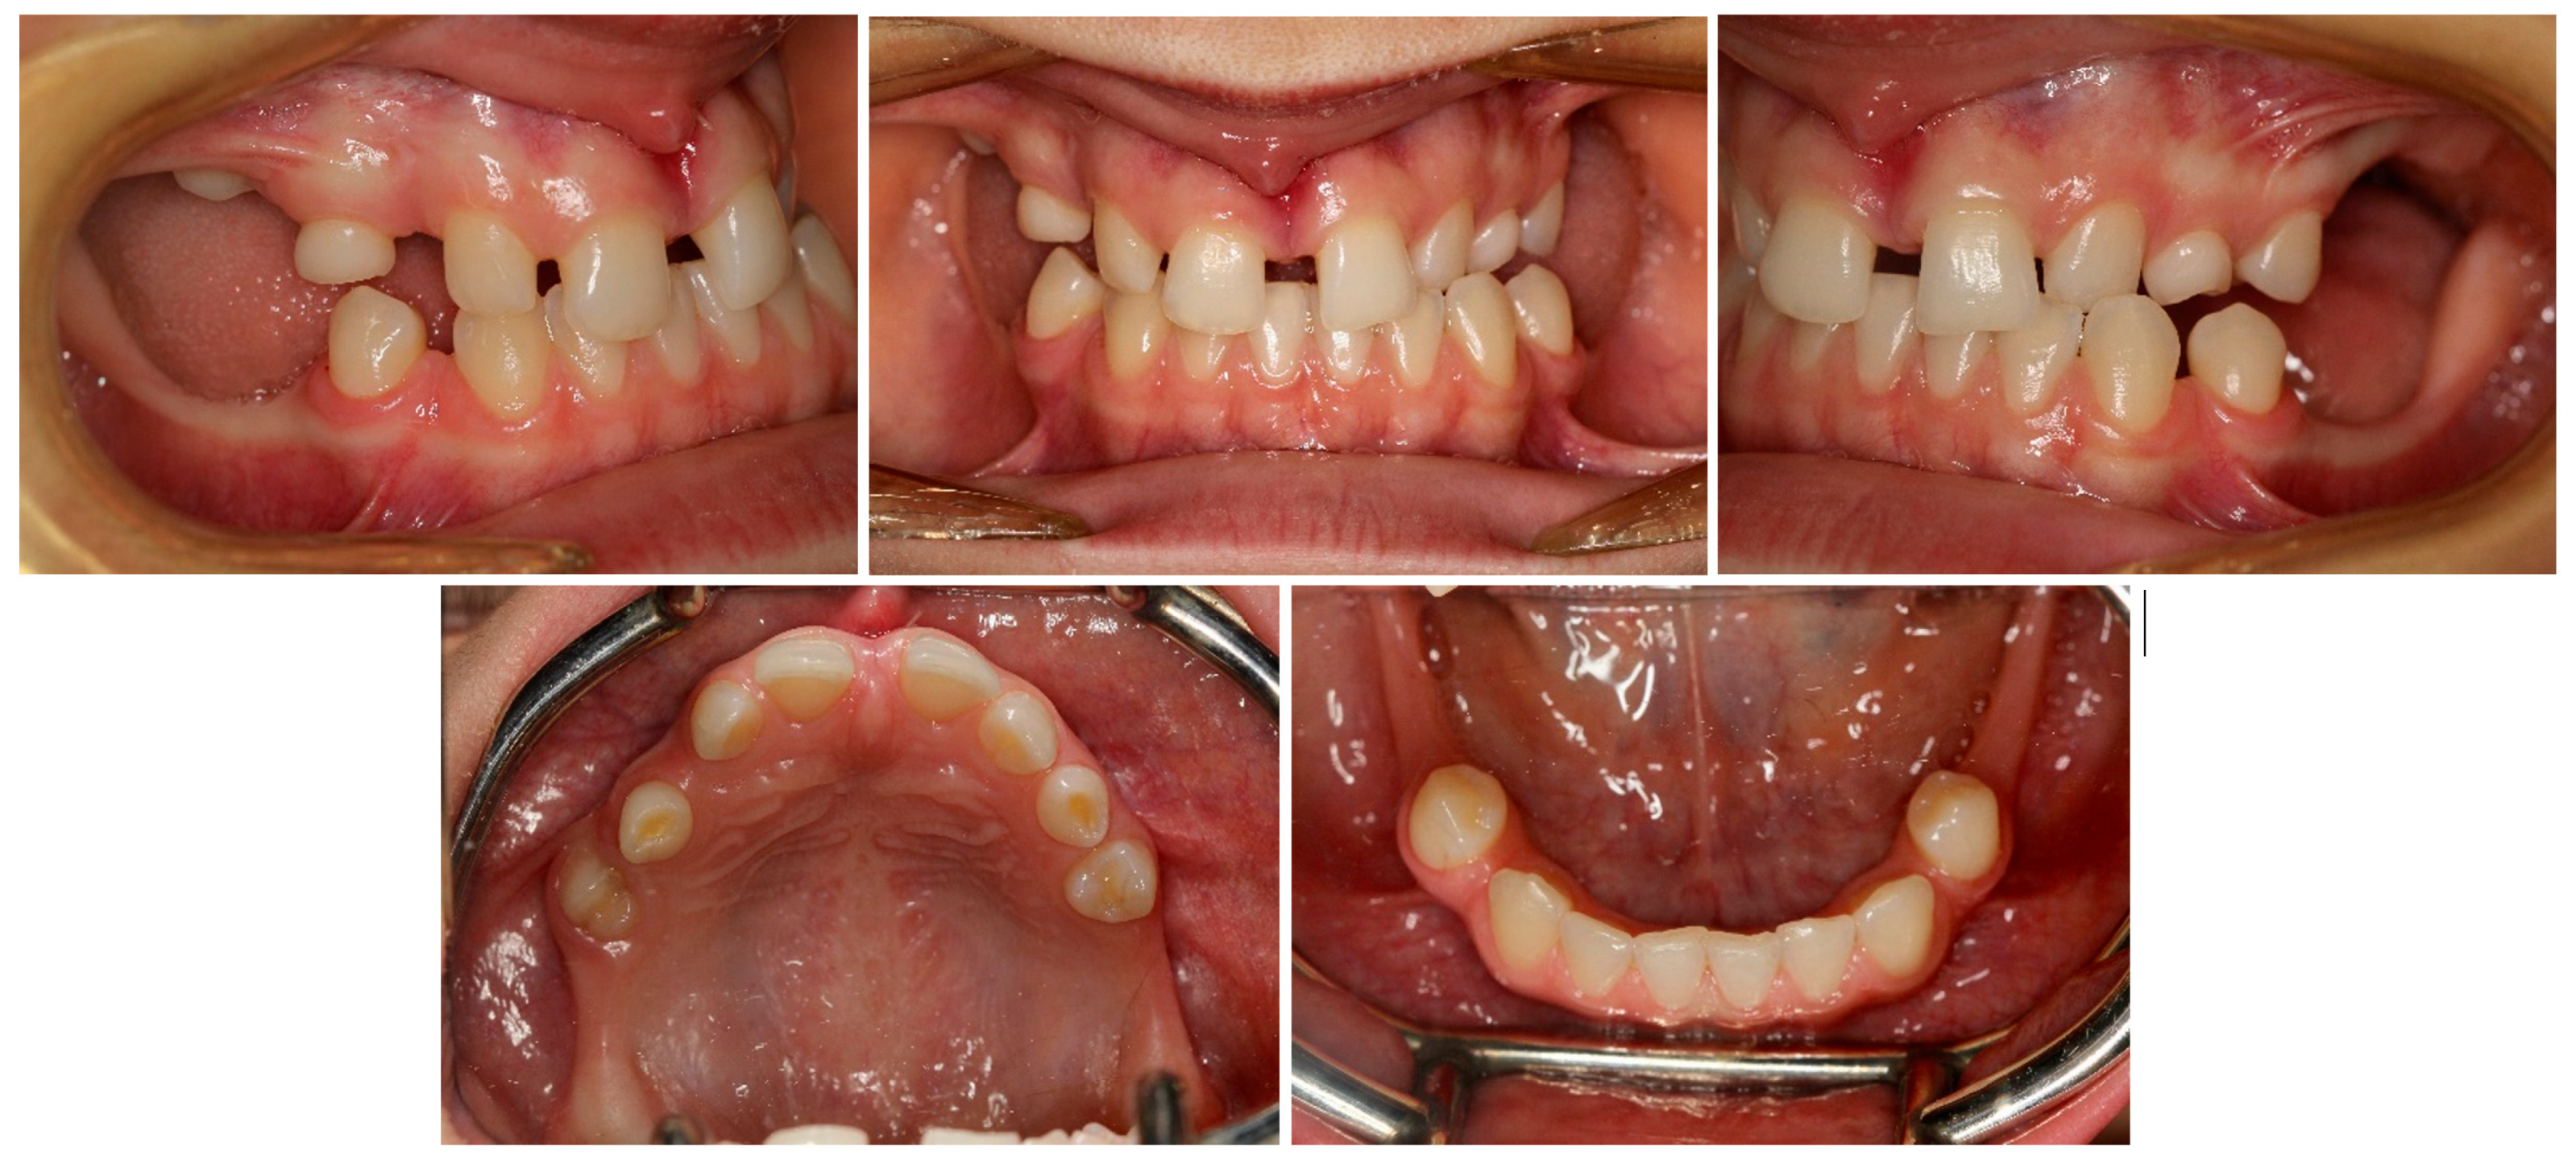

| October 2017 | PDCs’ surgical exposure—open technique; brackets bonded on PDCs; MIs tomas®-pin SD 06 (Dentaurum, Ispringen, Germany) inserted in the palatal alveolar region; 0.016″ × 0.022″ TMA cantilevers activated in distal and downward direction (50 g) (Figure 6a,b). |

| November 2017 | Visible orthodontic movement—exclusion of primary ankylosis (Figure 6c). |

| December 2017 | Increased mobility and tenderness of PDCs, dismantlement of cantilevers, button on the buccal side of UL3 (derotation), power chains to move the teeth (Figure 6d). |

| January 2018 | Teeth stability improved; 0.017″ × 0.025″ TMA cantilever with activation in downward and buccal directions for UR3, power chain for distal movement and derotation of UL3. |

| February 2018 | Button on the buccal side of UR3 (derotation), power chains for distal movements and derotations (Figure 6e). |

| April 2018 | Extraction of the upper right deciduous canine due to the collision with movement of UR3; 0.017″ × 0.025″ TMA cantilever activated for buccal movement of UR3 (50 g) (Figure 6f). |

| June 2018 | Partial fixed upper SS appliance Equilibrium® 2 0.022″ in Roth prescription (Dentaurum, Ispringen, Germany), 0.016″ NiTi wire, continuous metal ligature to create space for UL3; cantilever activation (Figure 6g). |

| August 2018 | Bracket on tooth no. 24; 0.016″ NiTi wire and open coil spring to create space for UL3; extraction of the upper left deciduous canine. |

| October 2018 | New MI tomas®-pin SD 08 (Dentaurum, Ispringen, Germany) was inserted in the buccal surface of left alveolar ridge; 0.017″ × 0.025″ TMA cantilever for buccal movement of UL3 (50 g) (Figure 6h). |

| November 2018 | Mobility of the buccal alveolar MI, the miniscrew was tightened and left to stabilize for a month; tooth no. 55 was extracted due to progressive reinclusion. |

| December 2018 | Buccal alveolar MI was lost and new MI tomas®-pin SD 10 (Dentaurum, Ispringen, Germany) was placed in the IZC; 0.017″ × 0.025″ TMA cantilever with buccal activation for UL3 (50 g). |

| February 2019 | Inflammation and submucous abscess in the IZC; MI removal; antibiotic. |

| April 2019 | New MI tomas®-pin SD 10 (Dentaurum, Ispringen, Germany) was inserted in the palatal suture and used as a direct anchorage with 0.017″ × 0.025″ SS cantilever and power chain for buccal movement of UL3 (50 g); 0.016” SS wire and bend-out for UR3 (Figure 6i). |

| May 2019 | Overcorrection of UR3 transversal relationship, 0.018″ SS wire and bend-out for tooth no. 22, new power chain from cantilever to UL3 for its buccal movement. |

| July 2019 | Tooth no. 22 in correct sagittal relationship; MI in the palatal suture used as an indirect anchorage: 0.017″ × 0.025 SS connection wire with tooth no. 24, 0.017″ × 0.025″ cantilever with buccal activation for UL3 (50g); 0.017″ × 0.025″ Cooper NiTi wire (Figure 6j,k). |

| March 2020 | The correct position of UL3; tooth no. 24 showed significant mobility; control panoramic X-ray: root resorption of tooth no. 24 (Figure 7); no possibility to conduct control visits on a regular basis due to COVID-19 pandemic—next appointment took place in November 2020. |

| November 2020 | 0.019″ × 0.025″ SS wire, torque expression, closure of spaces with power chain. |

| March 2021 | Removal of MIs, 0.021″ × 0.025″ TMA wire for torque expression in the upper arch; Fixed lower SS appliance Dentaurum Equilibrium® 2 0.022″ in Roth prescription (Dentaurum, Ispringen, Germany); 0.016″ NiTi wire; elastics 4 ½ oz. from palatal buttons on teeth no. 12 and 22 to the lower arch to correct the anterior crossbite (Figure 6l). |

| April–June 2021 | Further alignment of the lower teeth by means 0.017″ × 0.025″ NiTi, and next 0.019″ × 0.025″ SS; intermaxillary elastics 4 ½ oz and offset bends on teeth no. 12 and 22 were used to correct the anterior crossbite; elastic power chains for space closure. |

| August 2021 | Open sinus lift surgery with porcine bone-derived grafting material (The Graft™ bone substitute cancellous granules (Purgo Biologics, Seongnam, Republic of Korea) and BioCover™ resorbable collagen membrane (Purgo Biologics, Seongnam, Republic of Korea)) was performed on the right side of the maxilla. |

| March 2022 | Two dental implants were placed: tooth no. 14—Axiom® PX 3.4 × 12 mm (Anthogyr, Sallanches, France), tooth no. 15—Axiom® PX 3.4 × 10 mm (Anthogyr, Sallanches, France). |

| May–August 2022 | Finishing; control panoramic X-ray (Figure 8); 1st canine relationships and midline consistency; debonding of the brackets; fixed upper and lower retainers’ placement (0.027″ × 0.011″ 8-strand braided SS), tooth no. 24 was not fixed to the retainer due to increased mobility. |

| September 2022 | E-max (lithium desilicated ceramic) veneers on upper teeth; individual implant abutments (titanium pre-milled abutments) and implant-supported blocked crowns (zirconia veneered with porcelain using the cut-back technique) on dental implants; removable thermoformable retainer. |

| March 2023 | Retention phase: 10-month follow-up. Stability of treatment results; minimal opening of the spaces mesially to teeth no. 34 and 44; proper mobility of tooth no. 24. Bleaching of the lower teeth. |